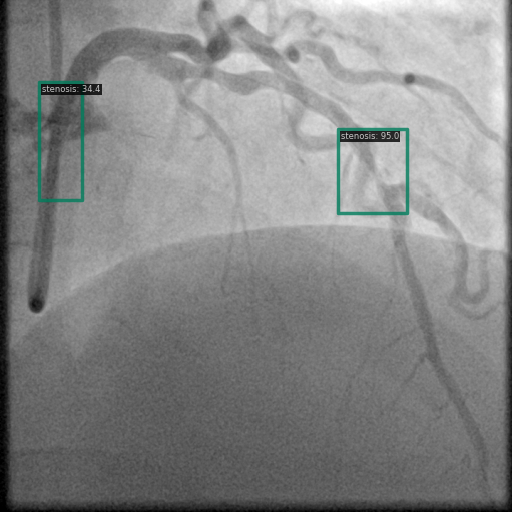

以下图像展示了每个模型在相同冠状动脉造影图像上的表现:

图6 Grounding DINO 的检测显示具有明确标签的高置信度狭窄检测。

3.2 Grounding DINO 检测模式

Grounding DINO 识别出了更多的区域,但有时由于过度检测导致预测混乱。该模型似乎利用其跨模态理解来检测更广泛的狭窄表现。如图 6 和图 9 所示,Grounding DINO 通常以不同置信度分数检测多个狭窄区域。虽然这增加了捕获所有狭窄区域的可能性,但同时也提升了假阳性的可能性。

图9 Grounding DINO 检测显示多个具有置信度分数的检测区域。